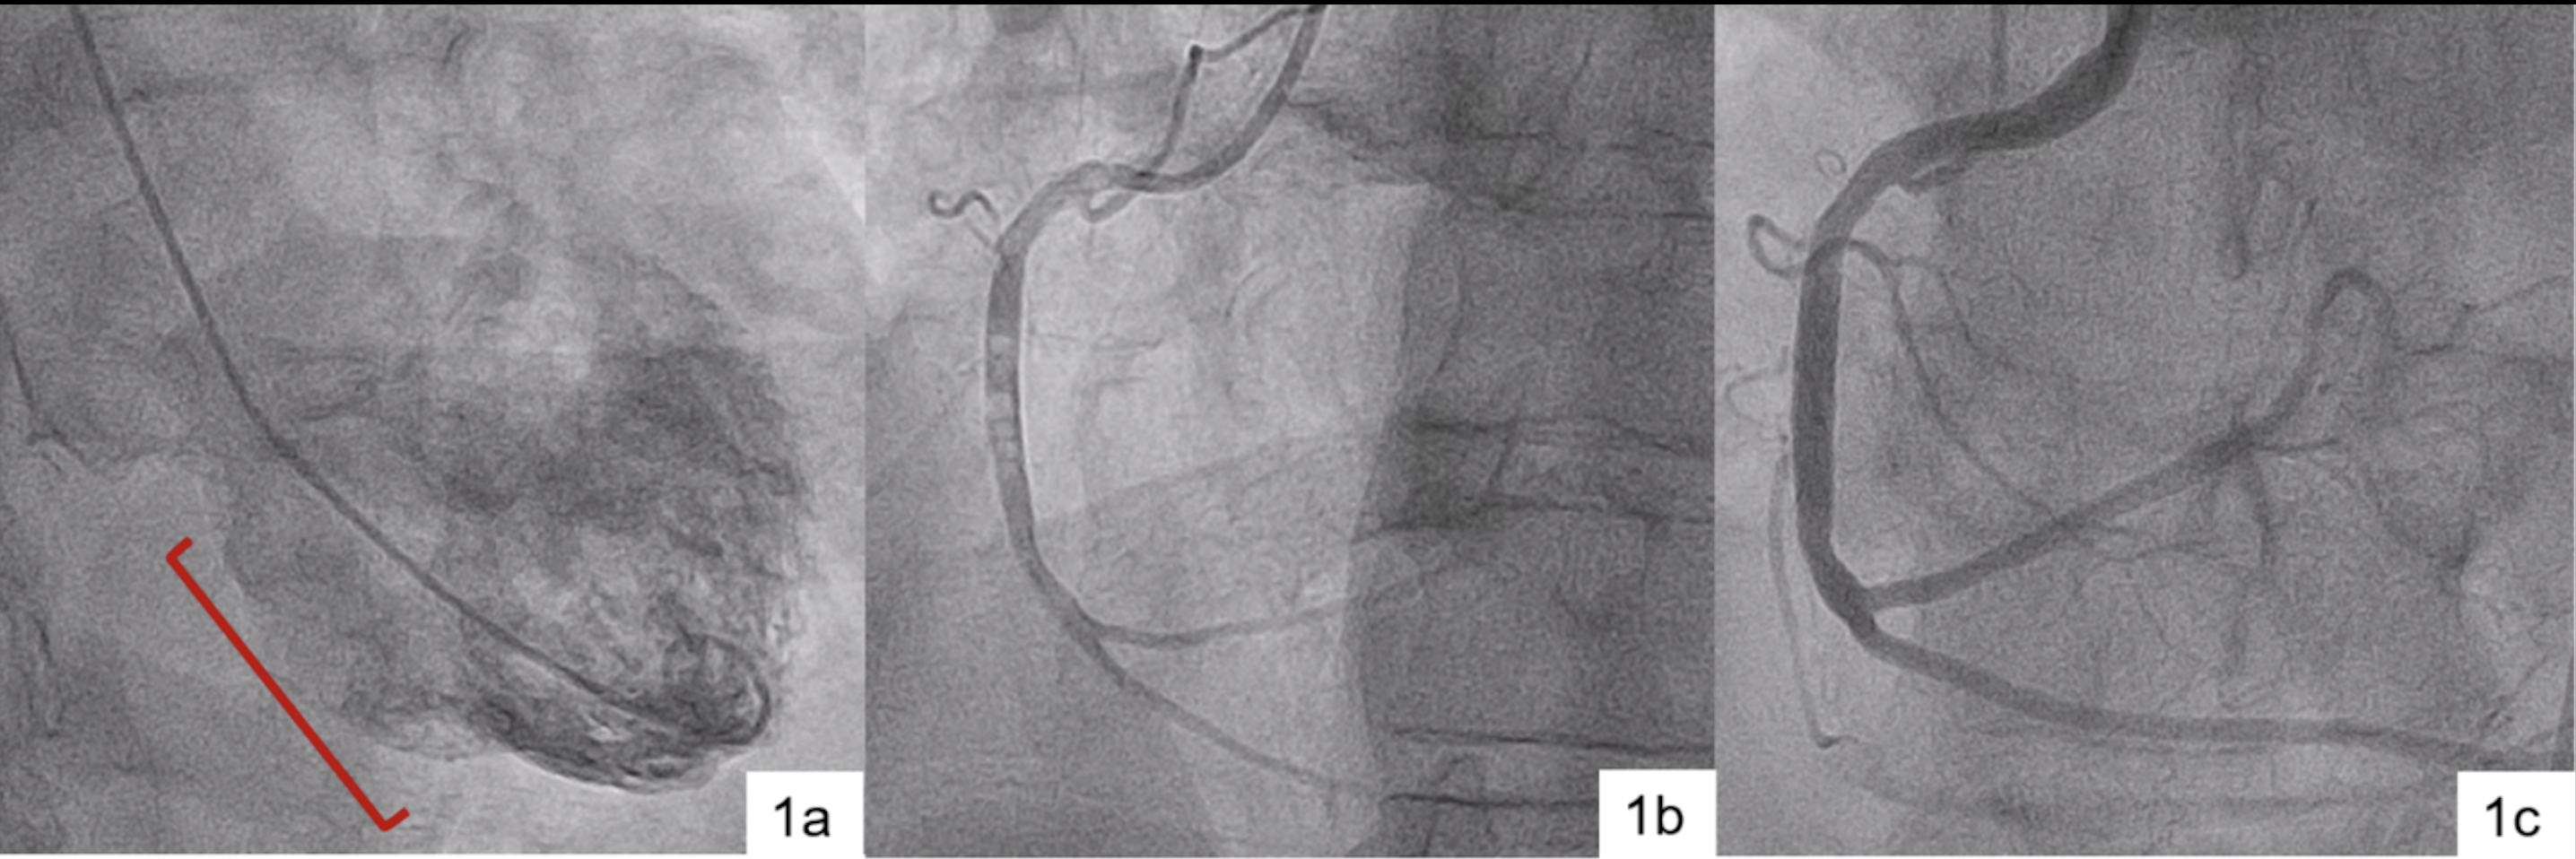

A 61-year-old male with mitral valve prolapse underwent preoperative LHC which showed a stenotic left anterior descending artery and normal right coronary artery (RCA). On the following left ventriculogram, significant inferior wall hypokinesis was observed, and the patient developed acute chest pain, ST elevations, and complete heart block (Figure 1a). Suspecting new RCA pathology, reevaluation revealed multiple air emboli and Thrombolysis In Myocardial Infarction (TIMI) grade 1 flow (Figure 1b). The RCA was flushed multiple times with heparinized saline, resolving the air emboli and restoring TIMI grade 3 flow (Figure 1c). At the procedure's end, the patient was pain-free and in sinus rhythm. A repeat transthoracic echocardiogram showed normal ventricular function without regional wall motion abnormalities. The patient was discharged without further complications.